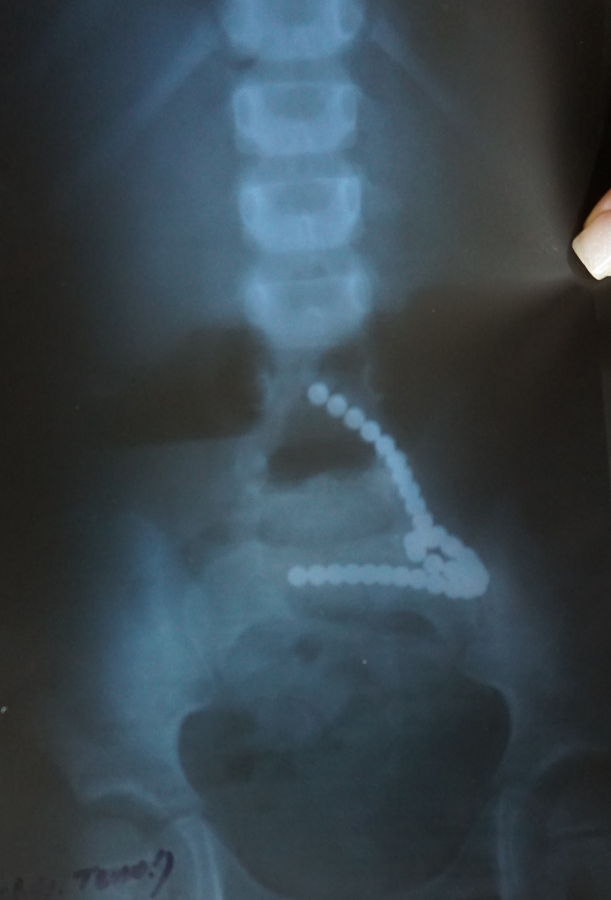

«Рентген, выполненный в стационаре, подтвердил наличие металлических бусин в отделе тонкого кишечника девочки. Только их оказалось значительно больше, чем сказал ребенок. Петля, спровоцировавшая острую кишечную непроходимость, состояла из 36 фрагментов!» – рассказали в больнице.